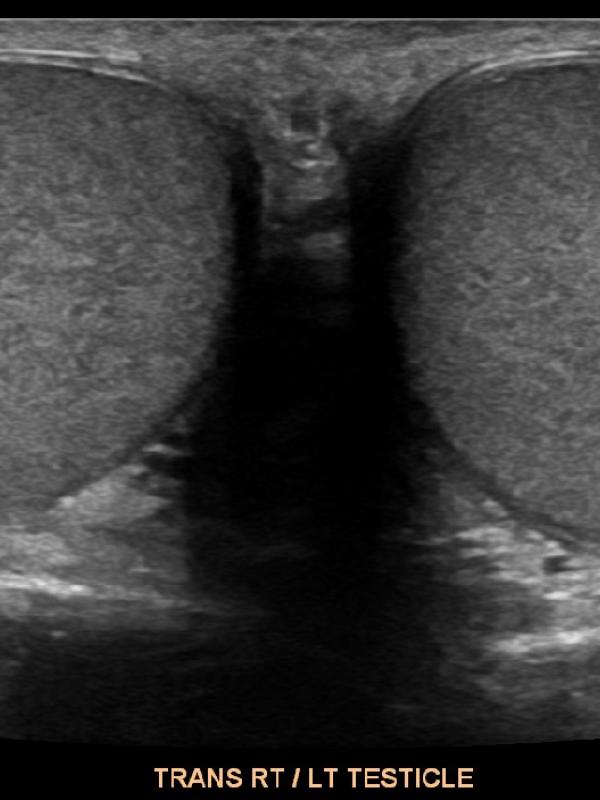

Scrotal ultrasound FAQ

Scrotal ultrasound

Ultrasound imaging is the primary diagnostic modality used to evaluate the scrotum/testicles. Referring providers will order a scrotal ultrasound for a number of reasons. The most common reasons are: testicular pain, a lump is discovered, or if a hernia is suspected. Undescended testis.

• Will the ultrasound of the scrotum and testicles be painful? No. The ultrasound exam will not be painful at all. The sonographer uses warm ultrasound gel and very light pressure from the transducer to image the testicles and scrotal contents.